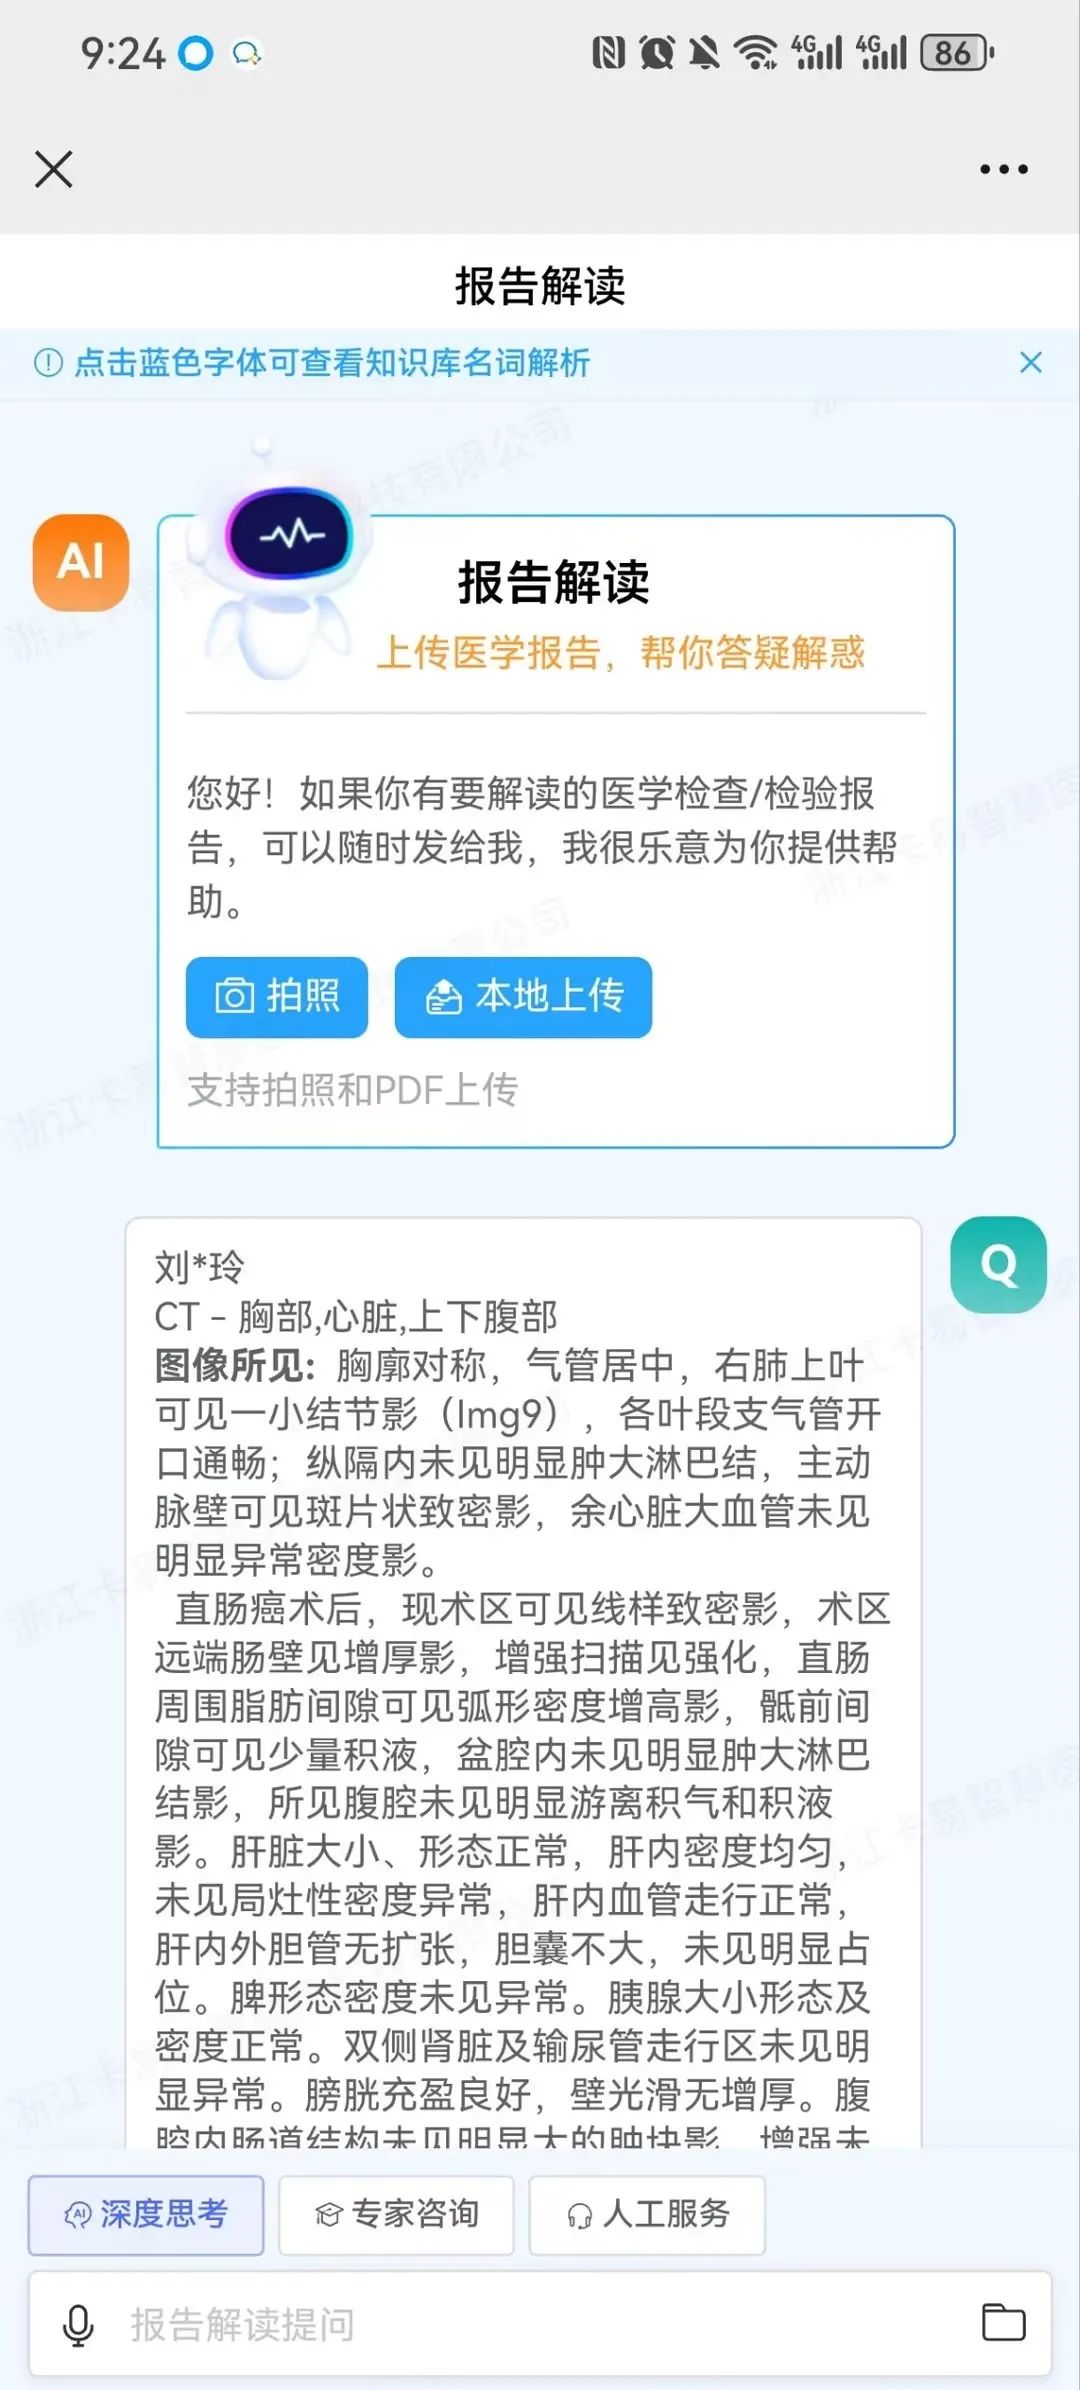

入口:打开无极云影像报告界面,底部提供患者相关智能化服务包括影像咨询、影像存档、名词解析、报告解读功能。

报告解读:通过DeepSeek提供贴心的影像报告解读服务,旨在帮助患者轻松理解检查结果和自身病情,通过将复杂专业的医学术语转化为通俗易懂的白话,有效缓解患者的焦虑情绪。平台支持拍照、自助上传报告PDF或报告图片以及语音解析等多种便捷方式,极大地提升了用户体验,让获取医疗信息变得更加方便快捷。

影像咨询:当患者对查看的影像或报告内容存在疑问时,可在报告界面直接发起影像咨询,借助DeepSeek获取关于检查流程、报告解读、病情咨询等方面的便捷、专业、优质且经济的建议与服务。若仍有不解,患者还可一键点击专家咨询,迅速发起线上问诊,由平台专家提供权威解答,这一流程不仅极大地优化了患者的就医体验,也显著提升了医疗服务的效率与质量。